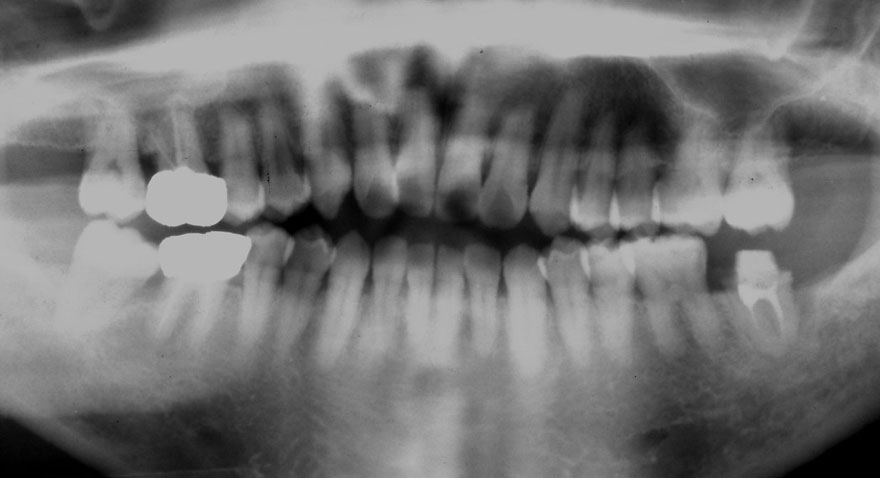

初診時 40歳 女性 平均歯槽骨喪失量:5.24mm

20年後 60歳

平均歯槽骨喪失量:5.79mm

21年間喪失量:-0.55mm

年間喪失速度:-0.027mm

(ケア頻度:1.23ヵ月ごと)